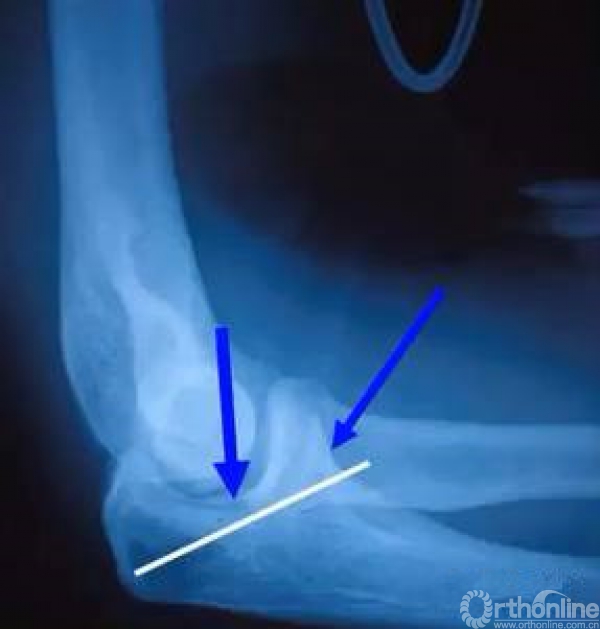

1.恢复尺骨关节面的C形;

2.稳定前侧的冠突部分;

3.内固定不要穿入关节;